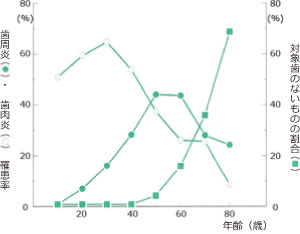

歯周病にかかりやすい時期

歯肉炎のピークは10歳代後半~30歳代前半、歯周炎のピークは50~60歳です。

対象となる歯がないヒトの割合は、60歳を過ぎると急速に増加していきます。